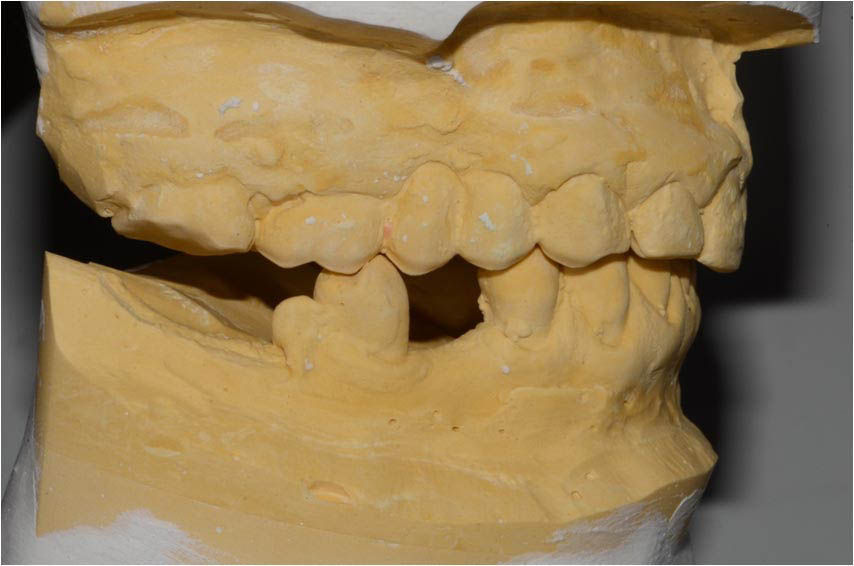

Model obtained from initial impressions, mounted in the articulator.